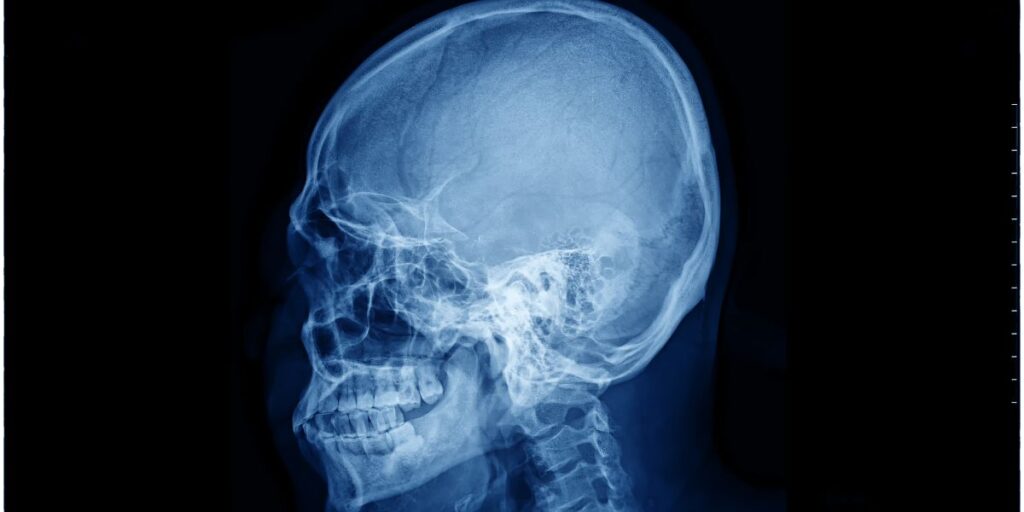

L’esame radiologico RX Mastoidi (Rocche Petrose/Forami Ottici) rappresenta un’indagine fondamentale per esplorare in modo approfondito l’anatomia dell’orecchio e identificare eventuali patologie. Grazie a questa tecnica di imaging, è possibile valutare le condizioni di strutture specifiche come le rocche petrose e i forami ottici. Questo articolo ti guiderà attraverso i principali aspetti dell’esame, spiegandone il funzionamento, le indicazioni e i vantaggi per i pazienti del Poliambulatorio S-Medical Group di Sora.

Il termine RX Mastoidi (Rocche Petrose/Forami Ottici) fa riferimento a una radiografia mirata che fornisce immagini dettagliate delle strutture ossee dell’orecchio. Le rocche petrose rappresentano la parte più densa e resistente dell’osso temporale, essenziale per la protezione dell’orecchio interno. I forami ottici, invece, sono passaggi naturali che permettono il transito di importanti nervi e vasi sanguigni. La valutazione di queste strutture tramite radiografia è cruciale per individuare anomalie o alterazioni legate a diverse condizioni patologiche.

Le immagini acquisite tramite RX Mastoidi (Rocche Petrose/Forami Ottici) offrono una panoramica dettagliata delle rocche petrose e dei forami ottici, permettendo di individuare:

• Accumuli di fluido o segni di infiammazione.

• Danni ossei o erosioni strutturali.

• Presenza di tumori o altre lesioni sospette.

• Malformazioni congenite che possono influire sulla funzionalità dell’orecchio.